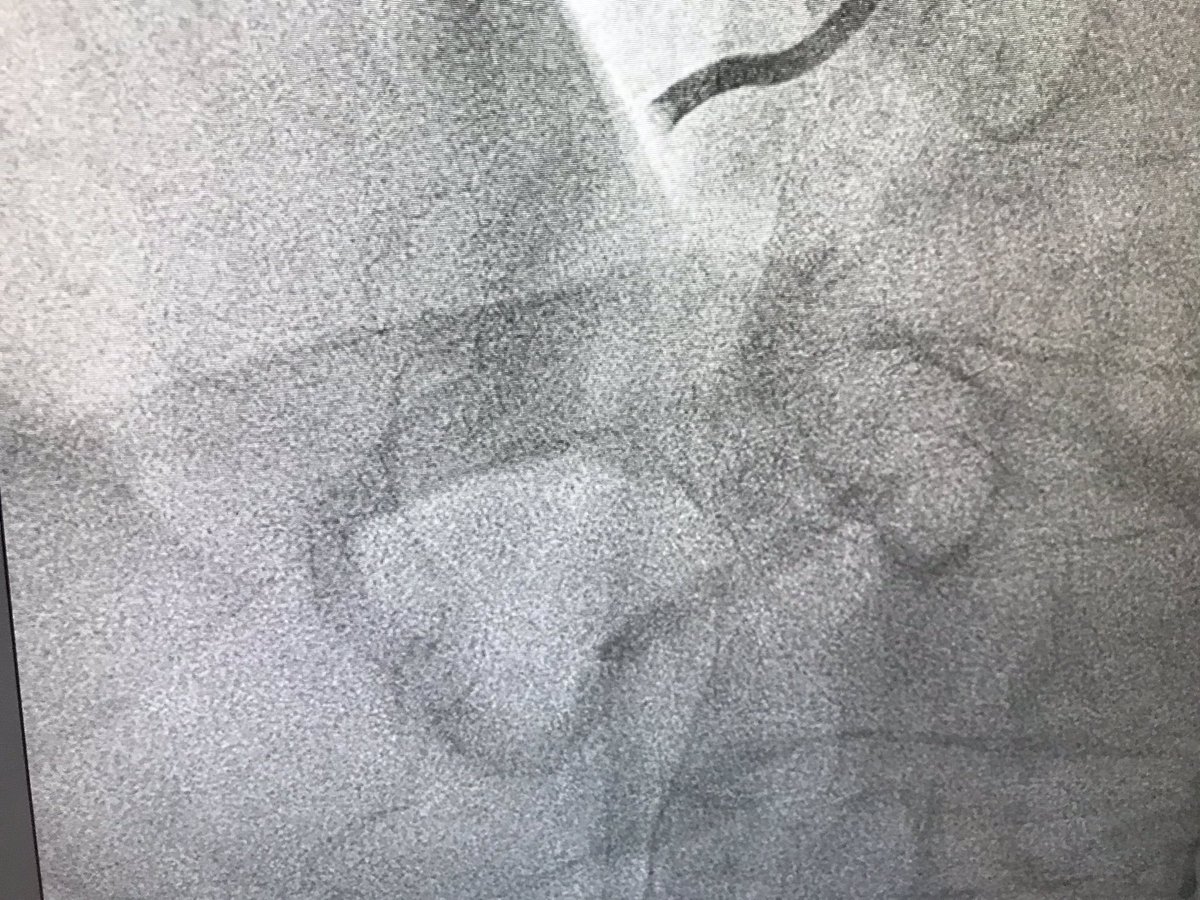

#RotaShock case 2. 82 year old male. PCI 2017 LAD and RCA in US. Complex ISR and new disease in RCA. Previous PCI attempt Nov 18 unsuccessful. NSTEMI presentation and subtotal calcified RCA @cghanratty @Almanfi_Cardio @ShockwaveIVL @BSCCardiology @jedicath

colum_owens's tweet image. #RotaShock case 2. 82 year old male. PCI 2017 LAD and RCA in US. Complex ISR and new disease in RCA. Previous PCI attempt Nov 18 unsuccessful. NSTEMI presentation and subtotal calcified RCA @cghanratty @Almanfi_Cardio @ShockwaveIVL @BSCCardiology @jedicath